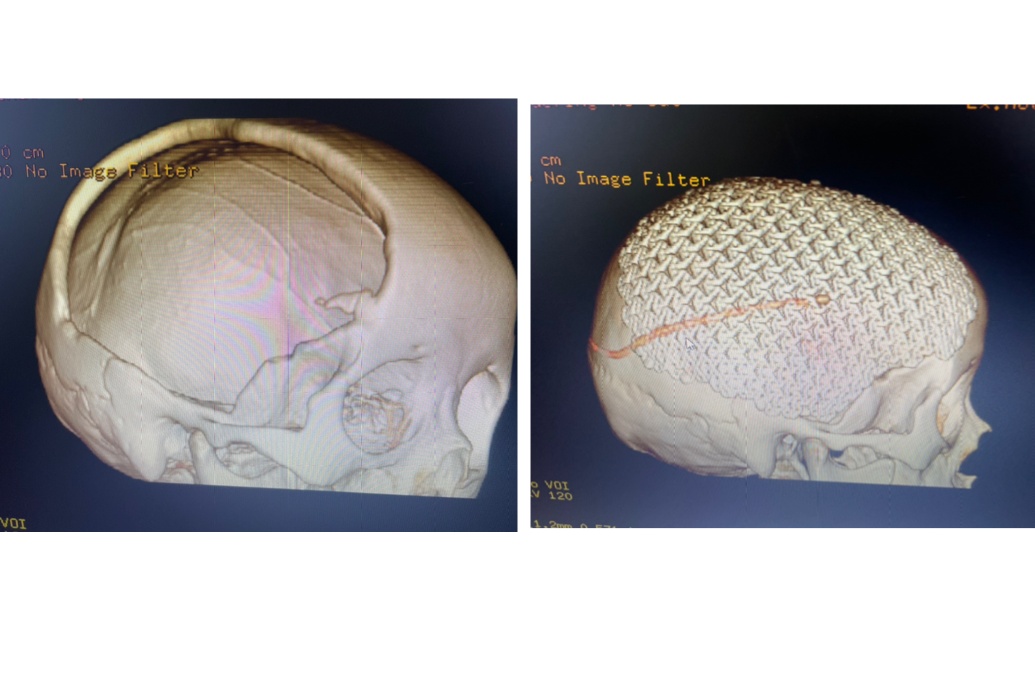

术后半年来院行颅骨缺损修补

钛网颅骨修补

是目前最常用的修补材料